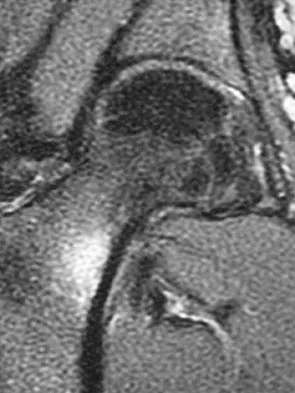

A 72-year-old woman who fell on her right shoulder while using a treadmill is now unable to elevate her right arm. An MRI scan is shown in Figure 7. What is the most likely diagnosis?

The MRI scan reveals a large chronic rotator cuff tear with retraction and fatty infiltration atrophy of the supraspinatus and infraspinatus tendons. This tear is responsible for the patient's severe weakness and inability to elevate the arm.